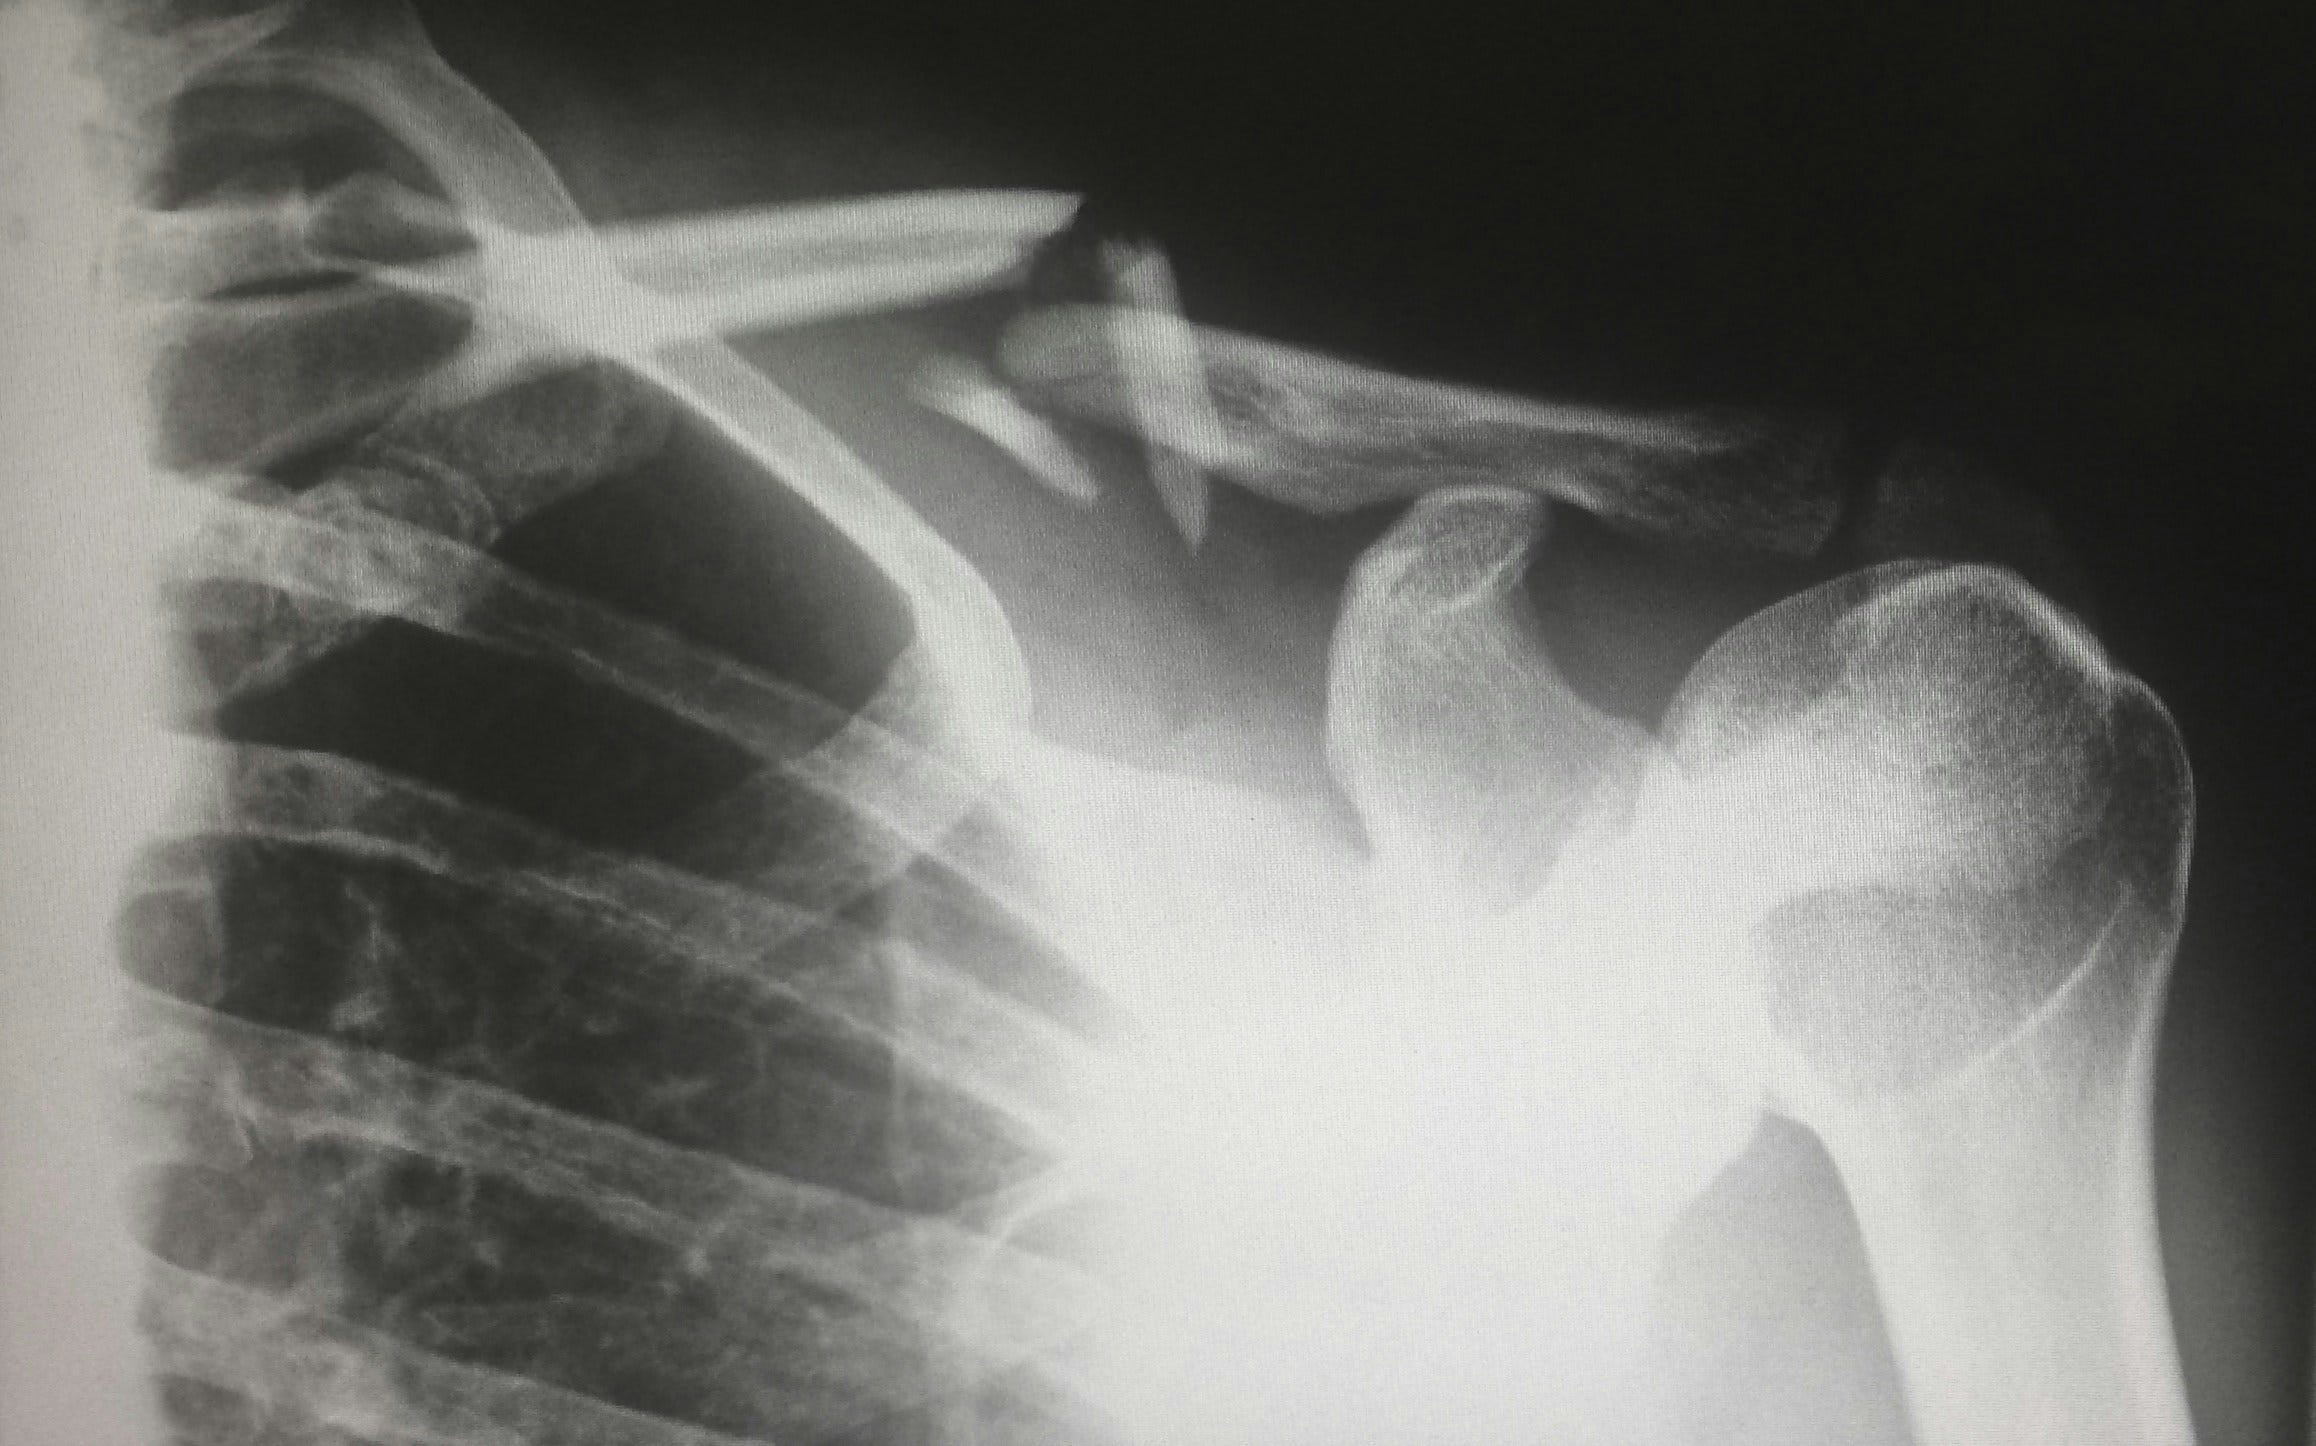

As I wrote in my first post, the GP thought the pain was caused by muscle spasm in her buttocks and lower back. Her private physio (who she sees about another issue) agreed. The GP did not refer her for an Xray as he said that if even it showed a fracture, the treatment would be the same – pain relief drugs and rest.

However, it was only after the NHS physio from the Falls team (from our local NHS trust) came to assess her that we realised the importance of an Xray. The physio said he could not advise on the correct treatment plan without being sure of the injury. This was one month after the fall. It took another 3 weeks for her to get an appointment at our local hospital for the Xray and another week to get the result, totalling 8 weeks after her fall.

The Xray found she did, in fact, have a compression fracture. Although this diagnosis didn’t change the medication, as the GP had said, it did give her peace of mind knowing what the injury was. We are puzzled why he didn’t refer her earlier, in the light of what the physio had said. He is an excellent GP from a very good surgery. That said, it doesn’t seem to be uncommon. A couple of other people I’ve spoken to have said their GP also refused an Xray for their elderly parent after a fall who continued to have problems long term.

My advice to anyone in this situation is to ask your parent to discuss this properly with their GP - to explore whether a lack of clear evidence of the injury will affect their physio plan.